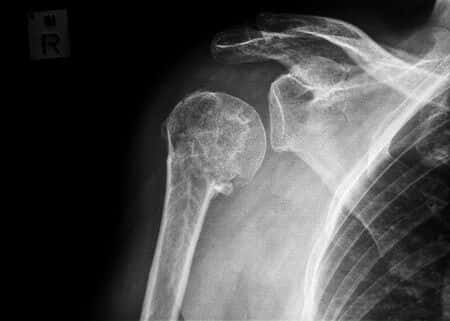

This case takes place in New Jersey and involves a man who was involved in a reasonably low-speed car crash. The man was stopped at an intersection when his vehicle was struck from behind by another driver. The driver claims to have suffered several debilitating and chronically painful injuries as a result of the accident, on which grounds he has sued the driver of the other car. The defendant claims that the speed of the impact was likely too low to result in the injuries that the plaintiff claims to have suffered, and that the plaintiff’s injuries must have existed before the crash occurred. To this end, the defense sought to retain a nuclear medicine expert witness to opine on the timing of the plaintiff’s injuries.

The success of this case will depend on the presence of underlying tendinosis and availability of the appropriate medical imaging before and after the accident.